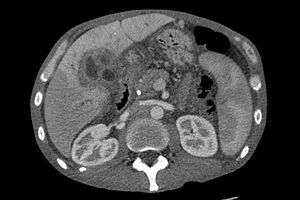

Ultrasound of the liver and biliary tree is often used as the initial imaging modality in patients with suspected obstructive jaundice.[41][42] Ultrasound can identify obstruction and ductal dilatation and, in some cases, may be sufficient to diagnose cholangiocarcinoma.[43] Computed tomography (CT) scanning may also play an important role in the diagnosis of cholangiocarcinoma.[44][45][46]

Imaging of the biliary tree

While abdominal imaging can be useful in the diagnosis of cholangiocarcinoma, direct imaging of the bile ducts is often necessary. Endoscopic retrograde cholangiopancreatography (ERCP), an endoscopic procedure performed by a gastroenterologist or specially trained surgeon, has been widely used for this purpose. Although ERCP is an invasive procedure with attendant risks, its advantages include the ability to obtain biopsies and to place stents or perform other interventions to relieve biliary obstruction.[7] Endoscopic ultrasound can also be performed at the time of ERCP and may increase the accuracy of the biopsy and yield information on lymph node invasion and operability.[47] As an alternative to ERCP, percutaneous transhepatic cholangiography (PTC) may be utilized. Magnetic resonance cholangiopancreatography (MRCP) is a non-invasive alternative to ERCP.[48][49][50] Some authors have suggested that MRCP should supplant ERCP in the diagnosis of biliary cancers, as it may more accurately define the tumor and avoids the risks of ERCP.[51][52][53]